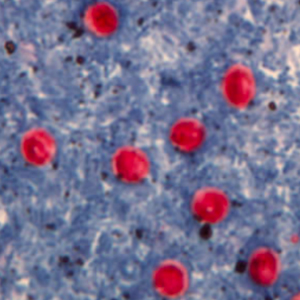

Les oocystes de cryptosporidie ne se colorent pas au Lugol. Ce sont des petites structures rondes mesurant entre 4 et 6 μm de diamètre, réfringentes. Leur contenu n’est pas visualisable en microscopie optique. Leur identification nécessite une coloration de Ziehl-Neelsen modifiée ; ils sont alors colorés en rose-rouge sur un fond bleu-vert. Il n’est pas possible de distinguer les différentes espèces sans technique de biologie moléculaire (Hoffman, 2017).